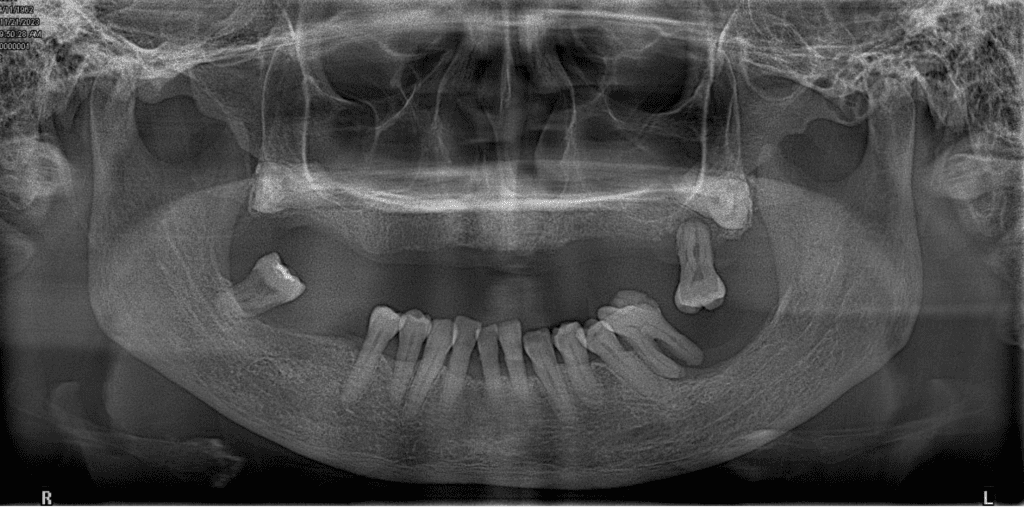

The findings from pulp sensibility test indicated that all teeth investigated are vital except for tooth 27. Dental Panoramic Tomogram (DPT) radiograph (Fig 5) of the patient reveals moderate resorption of the alveolar bone in both arches. Tooth 27, 36 and 48 exhibit widening of the periodontal ligament (PDL) space, discontinuity of the lamina dura at the apices, and vertical and horizontal bone loss up to apical third of the root with furcation involvement. Tooth 41 is missing. Additionally, radiopaque areas in the regions of tooth 18 and 28 are indicative of impacted teeth. Intraoral periapical (IOPA) radiograph (Fig 6) was taken to confirm these findings.